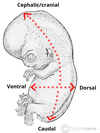

orange: flexion

blue: extension